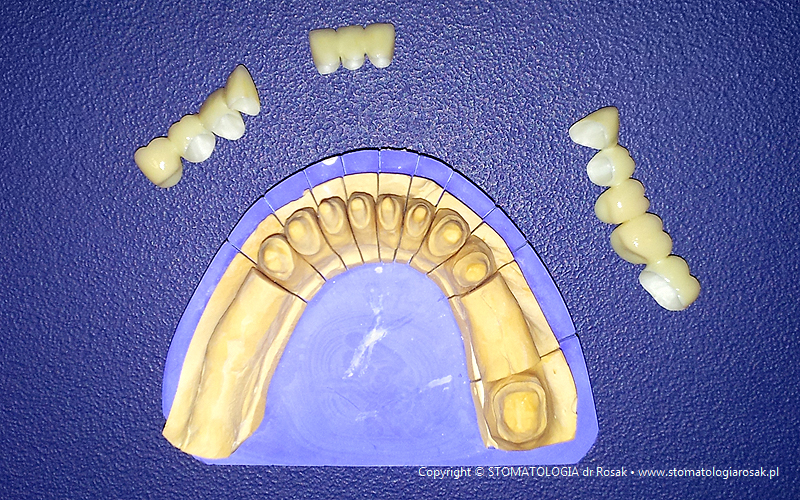

| 5e. Gotowy most porcelanowy górny i próba struktury metalowej dolnej |

5f. Gotowe mosty porcelanowe |